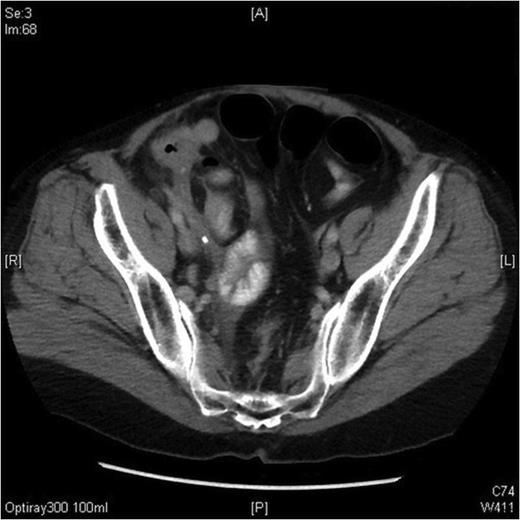

The CT scan of her abdomen did not reveal any free intraperitoneal gas however suggested inflammatory changes in the terminal ileum, caecum and ascending colon with mural thickening. The features reported were not typical of acute appendicitis but indicated possible active Crohns disease (Figure 1). As her clinical and haematological parameters did not improve with conservative treatment, a diagnostic laparoscopy after 48 hours was performed. Intraoperative findings were of free fluid in the pelvis and an inflammatory mass involving the terminal ileum with a perforated, grossly inflamed appendix. The patient underwent a laparoscopic appendicectomy and made an uneventful recovery being discharged home a few days later.

CT scan demonstrating the presences of inflammation in the right iliac fossa, with some distension of the appendix tip